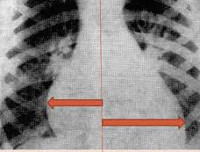

При рентгенографии органов грудной клетки выявляется кардиомегалия, изменение формы сердечной тени, усиление легочного рисунка за счет венозного застоя, признаки интерстициального отека легких. Результаты УЗИ сердца у ребенка демонстрируют дилатацию полостей сердца, снижение сократительной активности миокарда левого желудочка и фракции выброса.